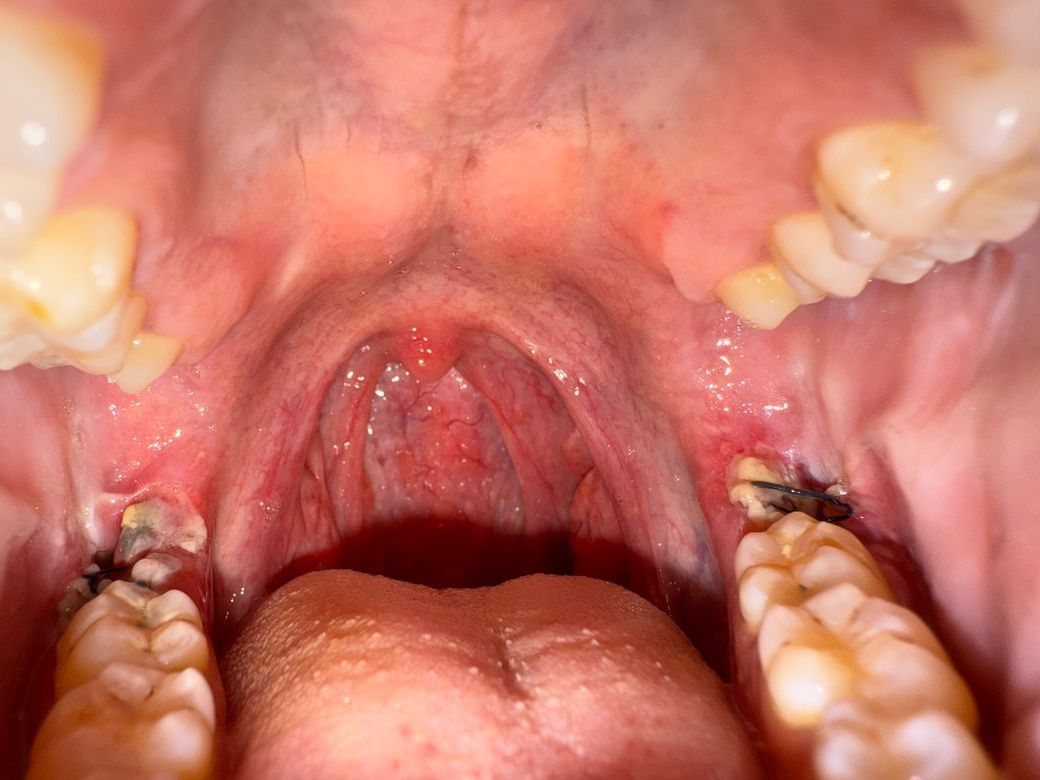

하악 매복사랑니 발치 6일차 입니다 불편함도 통증도 없습니다.

현재 상태로는 어느정도 회복된걸로 보면 될까요? 중요한 미팅(술자리)가 있어 음주,흡연을 피치 못할거 같아서요

발치한지 6일정도 지나셧고 통증도 없다면 크게 걱정은 안하셔도 될것같습니다. 실밥을 푸시고 나서만 관리를 잘하시면될것같습니다.

아직 온전히 회복되지 않았고, 잇몸 염증도 다소 있습니다 가급적 금주, 금연은 발치 후 2주까지 지켜주시면 좋습니다

실밥에 낀 음식물은 빼주시면 치유에 도움 됩니다